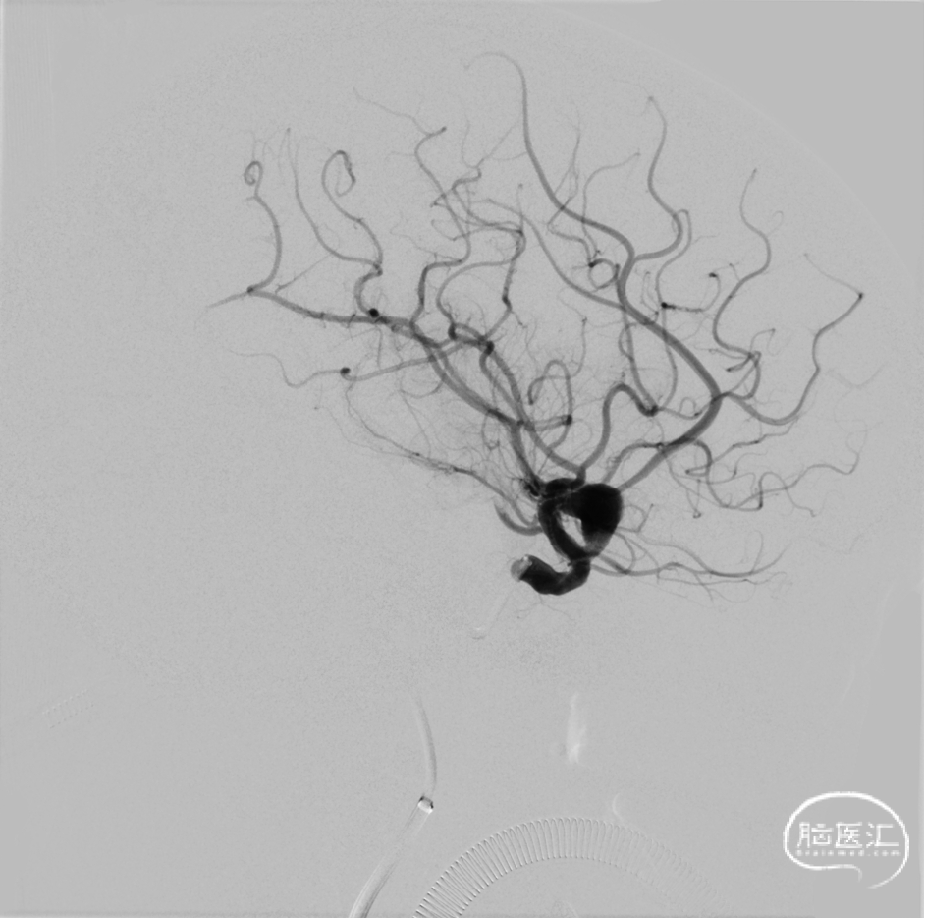

2024年4月1日 DSA

L ICA

L ICA 3D

AN长径9.14mm

远端血管大脑中直径2.34mm、近端颈内末端4.25mm

手术过程

回撤微导管造影

L ICA

Pre-OP

Post-OP